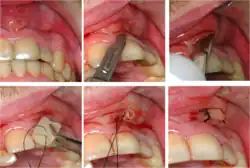

A general principle concerning dental abscesses is ubi pus, ibi evacua ("where there is pus, drain it"), which applies to any case where there is a collection of pus in the tissues (such as a periodontal abscess, pericoronal abscess, or apical abscess). The pus within the abscess is under pressure, and the surrounding tissues are deformed and stretched to accommodate the swelling. This leads to a sensation of throbbing (often in time with the pulse) and constant pain. Pus may be evacuated via the tooth by drilling into the pulp chamber (an endodontic access cavity). Such a treatment is sometimes termed open drainage. Drainage can also be performed via the tooth socket, once the causative tooth is extracted. If neither of those measures succeeds, or they are impossible, incision and drainage may be required, in which a small incision is made in the soft tissues directly over the abscess at the most dependent point. A surgical instrument such as a pair of tweezers is gently inserted into the incision and opened, while the abscess is massaged to encourage the pus to drain out. Usually, the reduction in pain when the pus drains is immediate and marked as the built up pressure is relieved. If the pus drains into the mouth, there is usually a bad or offensive taste.